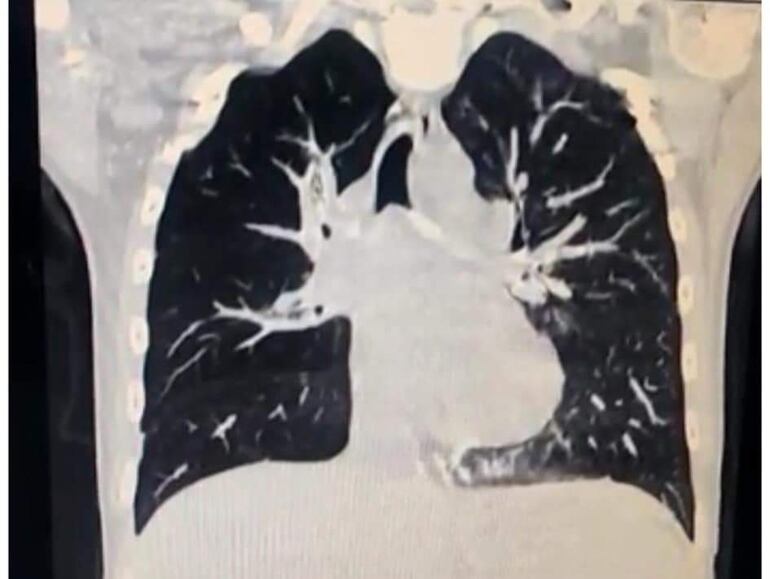

Los médicos examinaron a la paciente a través de una broncoscopía, que permitió diagnosticar que un cuerpo extraño obstruía las vías aéreas de la pequeña.

Posteriormente, se procedió a la extracción de dicho cuerpo a través de la misma técnica de diagnóstico. Gracias al procedimiento se constató que se trataba de una tapita de crema dental.